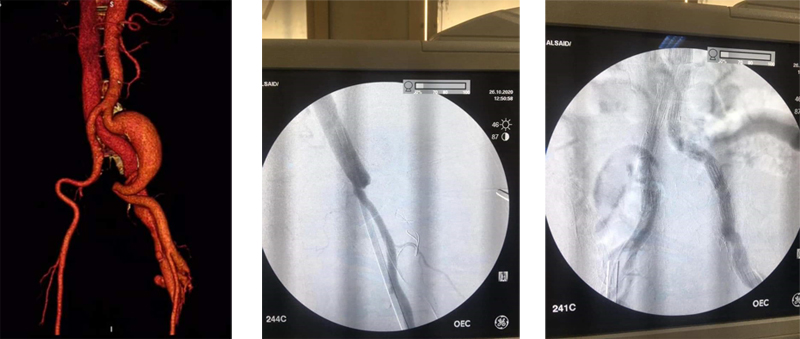

أعلن الأستاذ الدكتور/ علاء عطية - عميد الكلية عن نجاح فريق طبى بقسم جراحة الأوعية الدموية بكلية الطب جامعة اسيوط مكون من الأستاذ الدكتور/ أيمن حسب الله والأستاذ الدكتور/ أحمد حسن بكر والأستاذ الدكتور/ هيثم على حسن والأستاذ الدكتور/ محمود اسماعيل فى علاج أحد الحالات المعقدة والنادرة على مستوى العالم وهو مريض يعانى من ناسور شرياني وريدى فى الساق نتيجة طلق ناري منذ ١٥ عام وفى نفس الوقت يعانى من وجود تمدد ضخم بالشريان الحرقفى الأيسر.

وتم علاج المريض بتقنية مشتركة مابين التدخل الجراحى والقسطرة التداخلية حيث تم غلق الناسور بواسطة الربط الجراحي وإستخدام ملفات حلزونية وتم التعامل مع التمدد الشريانى بواسطة القسطرة التداخلية وتركيب الدعامات المغطاة.

وأوضح الأستاذ الدكتور/ مصطفى سعد - رئيس قسم جراحة الأوعية الدموية أن صعوبة الحالة فى تزامن وجود الناسور الشريانى مع التمدد الانيورزمى فى نفس الوقت وفى نفس الطرف مما يعرض حياة المريض للخطر.

وتعتبر إستخدام التدخل الجراحى مع القسطرة التداخلية هى الحل الأمثل فى مثل هذه الحالات.